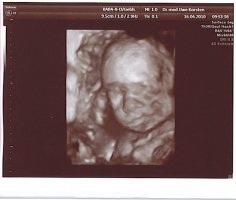

Tolle Fotos hier übrigens. Stelle mal ein paar neue von unserer Kleinen rein. Am Freitag hat sie sich das erste Mal bequemt, ihr Gesicht zu zeigen. Ich war echt fasziniert. Es ist so schön, dass Baby zu sehen. Bin jetzt schon total verliebt. Was soll das erst werden, wenn sie da ist?! 😛feif

• 8.jpg

8.jpg

82,3 KB · Aufrufe: 426

• 9.jpg

9.jpg

78,3 KB · Aufrufe: 424

• 10.jpg

10.jpg

85,3 KB · Aufrufe: 428